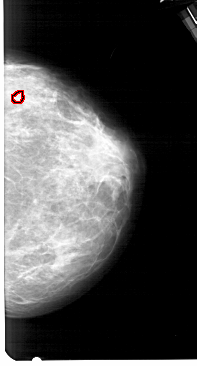

A_1546_1.LEFT_CC

LEFT_CC LINES 5101 PIXELS_PER_LINE 2791 BITS_PER_PIXEL 12 RESOLUTION 43.5 NON_OVERLAY

FILE: A_1546_1.RIGHT_CC.OVERLAY

TOTAL_ABNORMALITIES 1

ABNORMALITY 1

LESION_TYPE CALCIFICATION TYPE PLEOMORPHIC DISTRIBUTION CLUSTERED

ASSESSMENT 4

SUBTLETY 1

PATHOLOGY BENIGN

TOTAL_OUTLINES 1

BOUNDARY